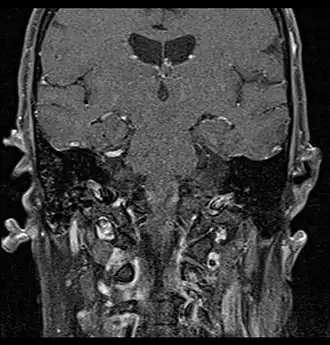

Primary treatment for this cancer, regardless of body site, is surgical removal with clean margins. This surgery can prove challenging in the head and neck region due to this tumor's tendency to show a perineural discontinuous growth, meaning that it follows nerves and different "nests" of the tumor can exist without a connection to the original tumor. Therefore, MRI-images should be analysed following nerve tracts up to the brainstem. Adjuvant or palliative radiotherapy is commonly given following surgery. For advanced major and minor salivary gland tumors that are inoperable, recurrent, or exhibit gross residual disease after surgery, fast neutron therapy is widely regarded as the most effective form of treatment.[13][14][15][16] Chemotherapy is used for metastatic disease. Chemotherapy is considered on a case-by-case basis, as data on the positive effects of chemotherapy are limited. Clinical studies are ongoing, however.

Coronal MRI showing right parotid adenoid cystic carcinoma with perineural spread of tumor: The tumor originates in the right parotid gland and spreads along the trigeminal nerve via the auricuotemporal branch extending intracranially through the foramen ovale at the skull base towards Meckel's cave. -